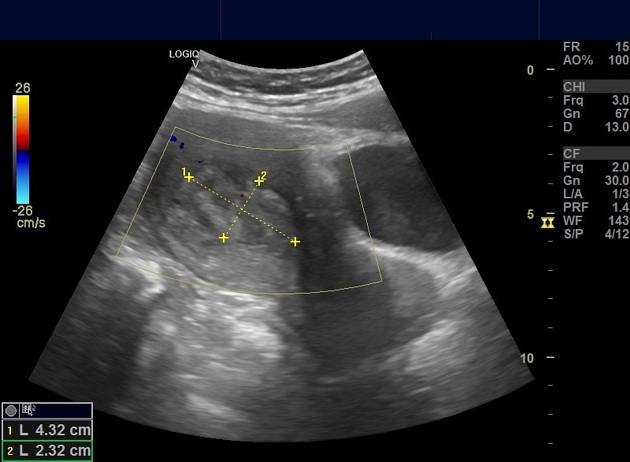

Polyp nội mạc tử cung

» Thông tin: Nữ giới – 40 tuổi.

» Lâm sàng: Rong kinh.